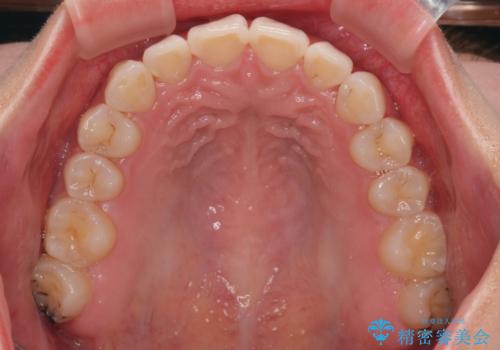

前歯の捻れを改善するとともに、口元が少しでも引っ込むように治療計画を立て、仕上げることができました。

長時間の装着を徹底し、遠方からの通院にもかかわらずしっかりと通院いただき、予想よりも早く治療を終えることができました。